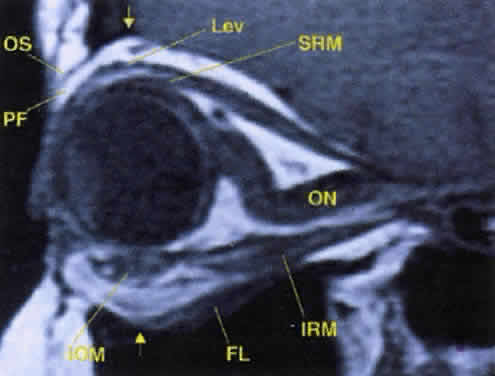

Fig. 17. The optic nerve (ON). A parasagittal MR image demonstrates the 7-mm excess of intraorbital optic nerve, seen as an S shape. Also note the perpendicular relation of the inferior oblique muscle (IOM) to the inferior rectus muscle (IRM). Other findings of anatomic interest in this image include the levator (Lev), the superior rectus muscle (SRM), the orbital septum (OS) arising from the arcus marginalis, and the preaponeurotic fat pad (PF) between the septum and the levator. Note that the orbital floor (FL) is angled upward by 15° to 20° from anterior to posterior.

As the levator palpebrae superioris (levator) muscle and superior rectus muscle course anteriorly, diffuse connections form to the orbital roof, creating an effective suspensory system. Further, diffuse fascial connections form between the levator and superior rectus muscles, allowing precise coordination of upper eyelid retraction with upgaze. Note that on imaging studies, the close association of these two muscles often makes them look like a single anatomic unit; the term “levator-superior rectus complex”is often found in radiologic reports (see Fig. 17). A fascial sling forms beneath the superior rectus muscle to provide suspensory support for the superior ophthalmic vein.